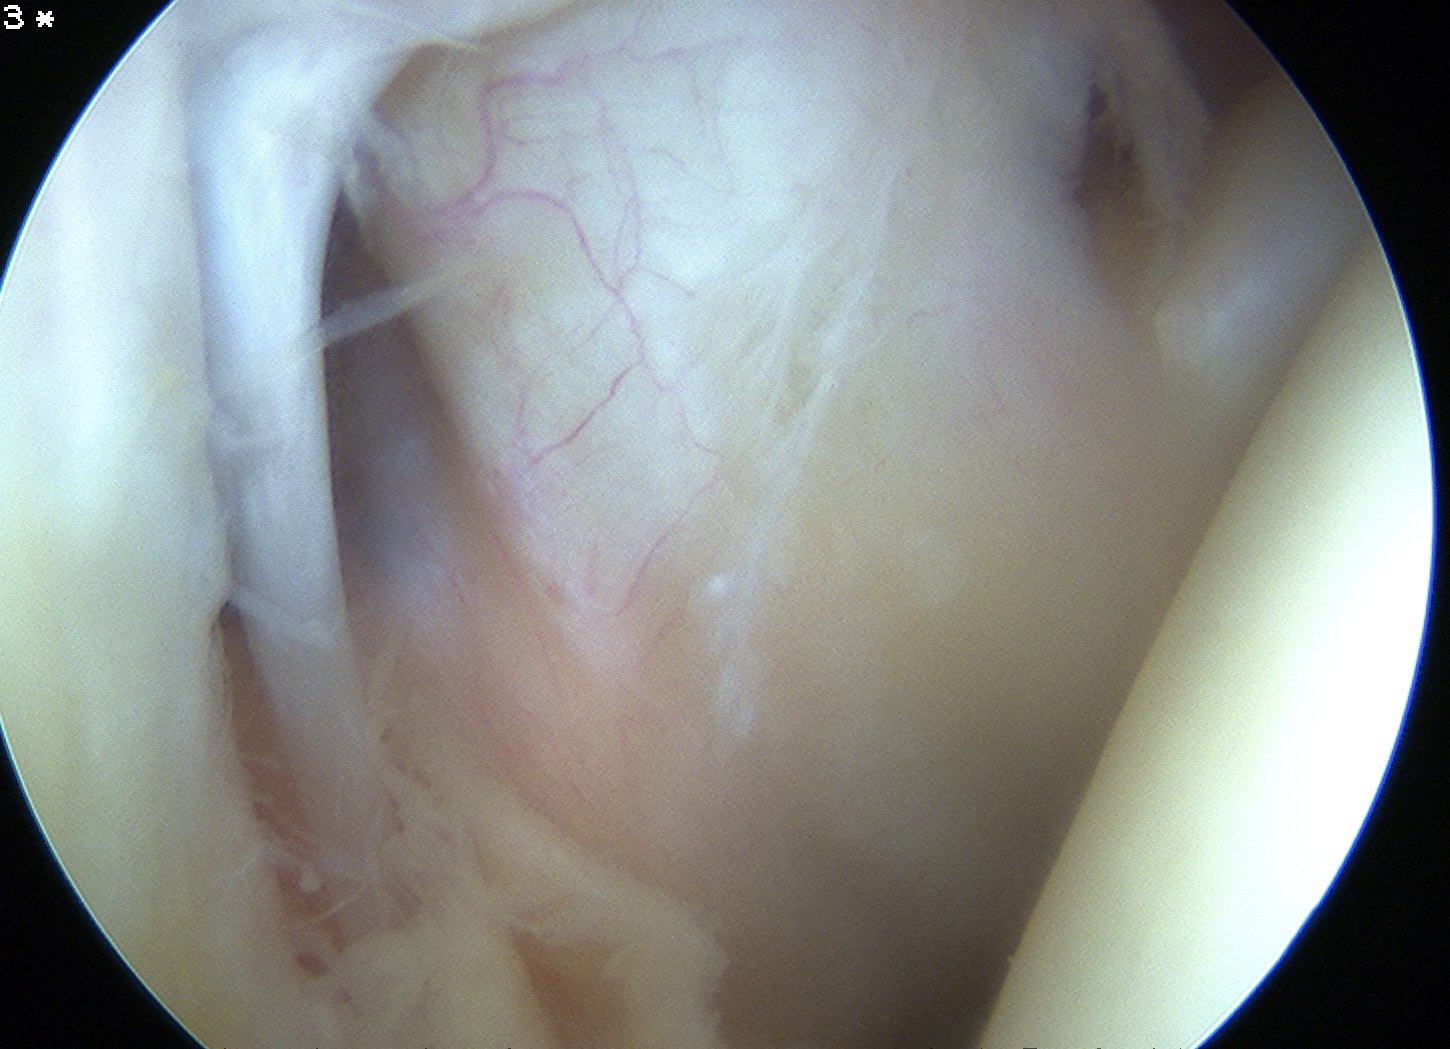

| Superior glenohumeral ligament (SHGL) | Middle glenohumeral ligament (MGHL) |

|

Origin: Supraglenoid tubercle glenoid and coracoid Insertion: Proximal aspect medial edge lesser tuberosity of the humerus |

Origin: Distal aspect lesser tuberosity of humerus Insertion: Posterior aspect subscapularis |

Runs perpendicular to the middle GHL |

Crosses subscapularis vertically Variable size and shape in different people Cord like / leaf like / vestigal |

Stabilizes the long head of the biceps in its groove Limits external rotation of the humerus |

Limits external rotation with arm by side |

![]() |